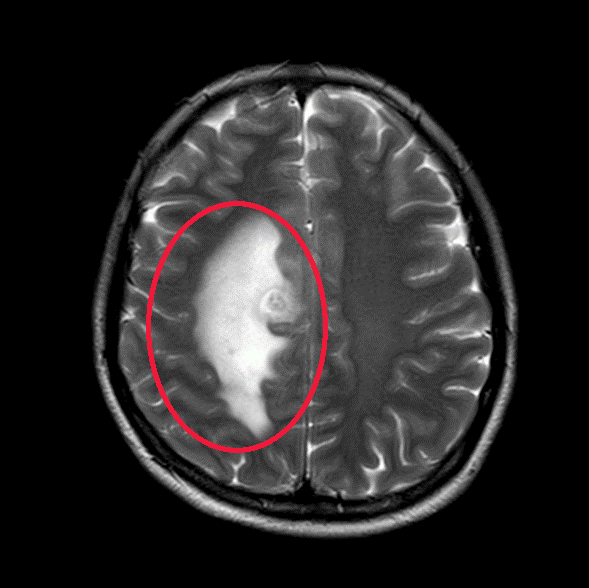

于是

我们给这位年轻患者口服了靶向药

短短一个月

患者肺部和脑部肿瘤就出现明显退缩

随访至今

肺部、颅内、可见淋巴结、腹腔等

多处病灶完全缓解

患者日常生活无异于常人

我们对她能生存5年,甚至10年充满信心

可能更长

……

▲治疗前

▲治疗后1月

▲治疗后2年半